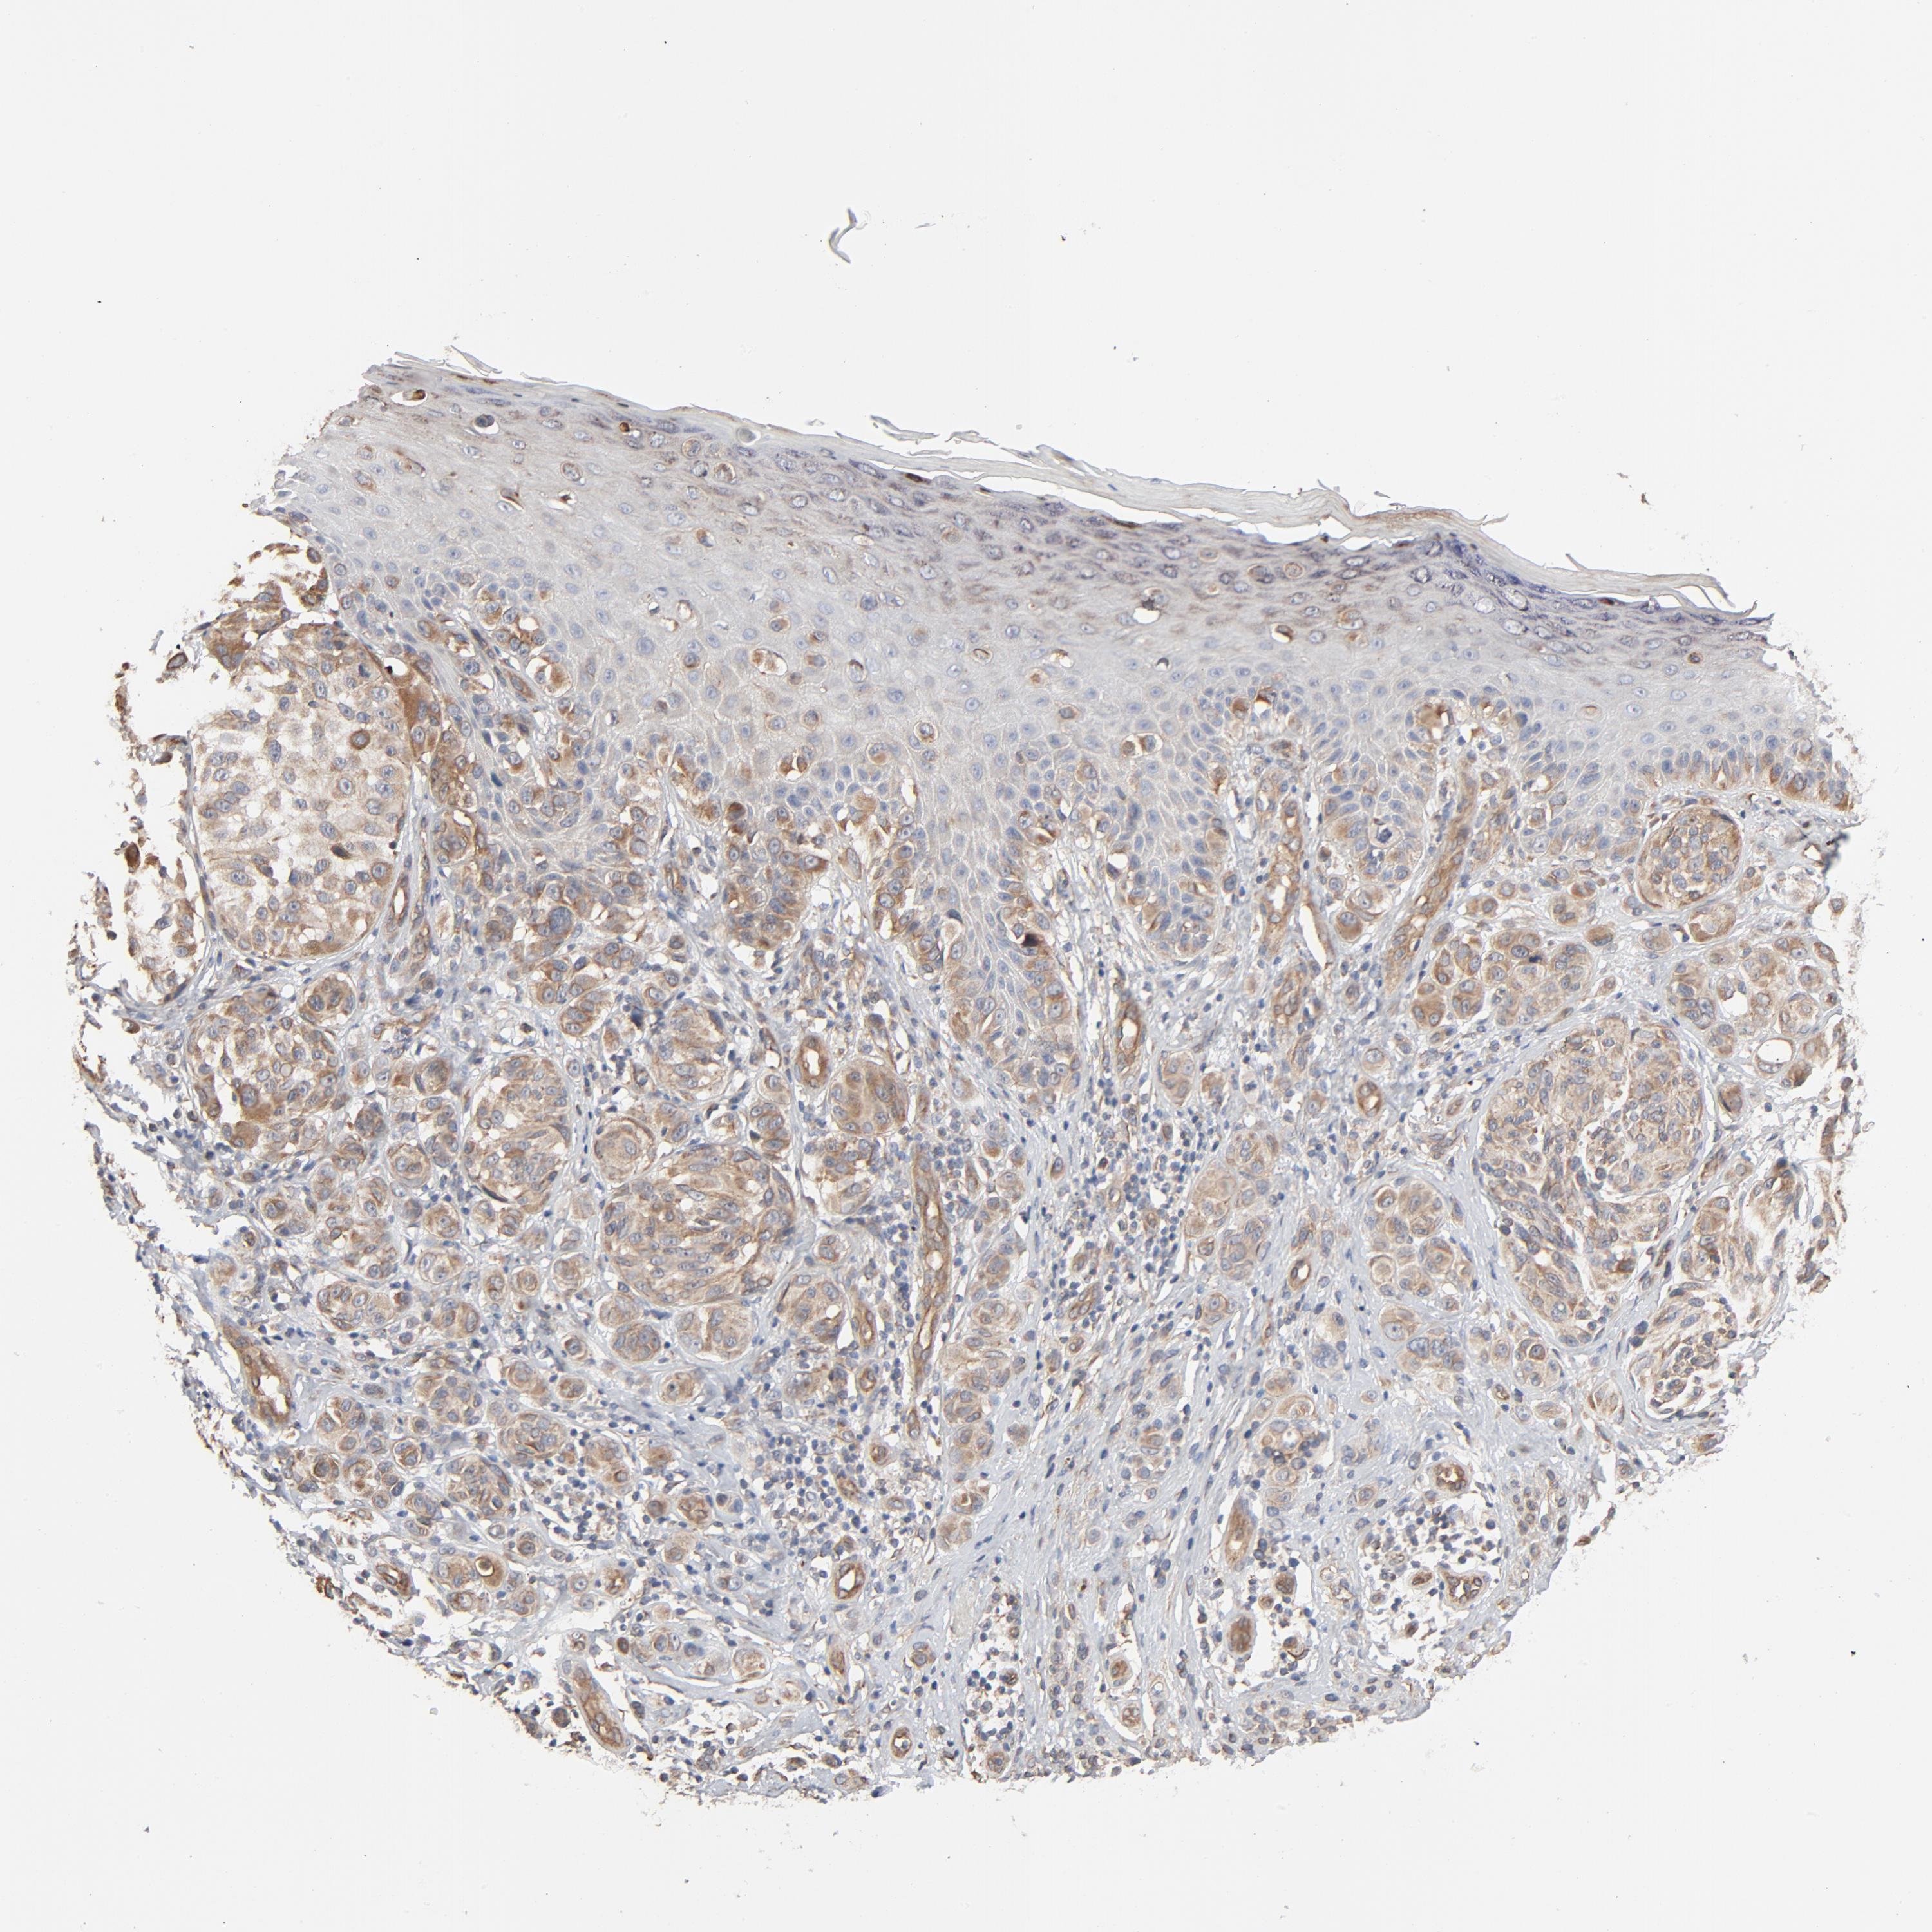

MELANOMA - Protein expressioni

A mouse-over function shows sample information and annotation data. Click on an image to view it in a full screen mode. Samples can be filtered based on level of antibody staining by selecting one or several of the following categories: high, medium, low and not detected. The assay and annotation is described here.

Note that samples used for immunohistochemistry by the Human Protein Atlas do not correspond to samples in the TCGA dataset.

Antibody stainingi

Antibody staining in the annotated cell types in the current human tissue is reported as not detected, low, medium, or high, based on conventional immunohistochemistry profiling in selected tissues. This score is based on the combination of the staining intensity and fraction of stained cells.

Each image is clickable and will lead to virtual microscopy that enables deeper exploration of all samples and also displays staining intensity scores, fraction scores and subcellular localization as well as patient and tissue information for each sample.

Antibody HPA003747

Antibody HPA019769

Malignant melanoma, NOS

Malignant melanoma, Metastatic site